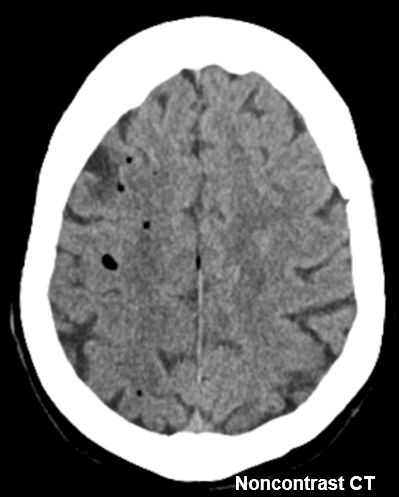

#AJNRcc >> November 27, 2023 >> What is the diagnosis for this 9-year-old boy with dysarthria, tremor, motor tics, and decreased scholastic performance for 1 year? Submit your answer at ow.ly/KikS50Qcyi2